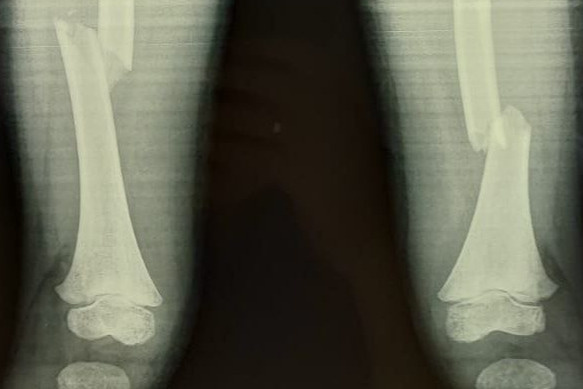

— Здесь беда была в чем. Шейка бедра была сломана — а это то, за счет чего мы вообще опору даем и благодаря чему есть движение в тазобедренном суставе. Плюс оскольчатый перелом был в дистальном отделе, где коленный сустав. Было большое количество отломков, нужно было всё застабилизировать. Был риск несращения, так как идет размозжение тканей вокруг. Был велик риск асептического некроза — когда кости не приживаются, — цитирует Минздрав Омской области врача — травматолога-ортопеда Максима Перфилова.